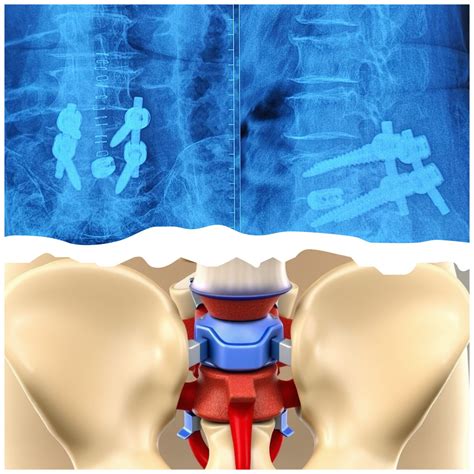

PLIF vs. TLIF: Which is Better?